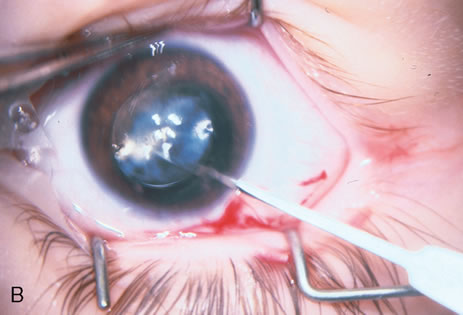

When phacoemulsification became available, it was quickly applied to the removal of children's cataracts because it provided the surgeon with better control of the flow of irrigating solutions and provided improved control of the aspiration flow and pressure.4 The instrument also added a new capability, that of being able to mechanically disrupt the lens nucleus and cortex to facilitate aspiration of the lens. Although the phacoemulsification instrument was helpful for removing lens cortex, it was ineffective in cutting or removing the posterior lens capsule. At the conclusion of the phacoemulsification procedure, the posterior capsule was left intact. When capsular opacification occurred, it was treated with a discission procedure, an operation that consisted of making a cut in the posterior capsule with a bent needle, a Ziegler knife, or a modification of the latter (Fig. 1). If the membrane was thick and resisted opening with a knife, an intraocular scissors was necessary to open the lens capsule.

The advantage of leaving the posterior capsule of the lens intact after cataract surgery is that it retains a barrier between the anterior chamber and vitreous. This prevents the vitreous from entering the anterior chamber, and it theoretically preserves the ocular anatomic relationships after cataract surgery. The disadvantage of leaving the posterior lens capsule intact is that when the capsule opacifies, a second procedure is needed to re-establish a clear visual axis. To achieve this, a second anesthetic is administered and an incision is made into the clear cornea. The chamber is deepened with a viscoelastic material and a knife or other instruments are introduced into the anterior chamber to cut or tear the posterior capsule so that the visual axis can be cleared (Fig. 1).